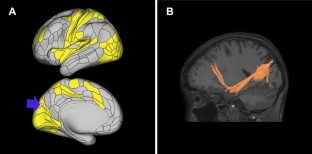

In the OpenNeuro (n = 68) and SchizConnect cohort (n = 195), there were 27.9% and 43.1% of parcellations, respectively, in the lower half of all ranks that displayed top quartile ranks. We noted three outstanding parcellations (L_V6, L_a10p, and L_7PL) in the OpenNeuro cohort that also appeared in the SchizConnect cohort. In the larger Schizconnect cohort, L_V6, L_a10p, and L_7PL had unexpected hubness in 3.08%, 5.13%, and 8.21% of subjects, respectively.